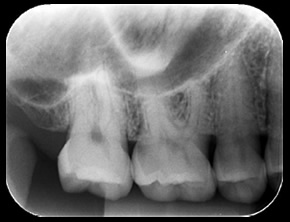

一般的な歯科用レントゲン

一般的な歯科用レントゲン画像は直線的に撮影した情報を見ることが出来ます